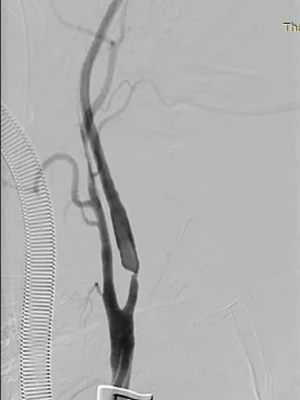

▲ 术前影像

在血管外科崔文军主任、安乾副主任、王浩医师紧密协作和美国芝加哥大学医学中心(University of Chicago Medical Center)Dr. Ross Milner 教授的现场技术指导下,手术团队精准操作,顺利完成了这台具有里程碑意义的TCAR手术。